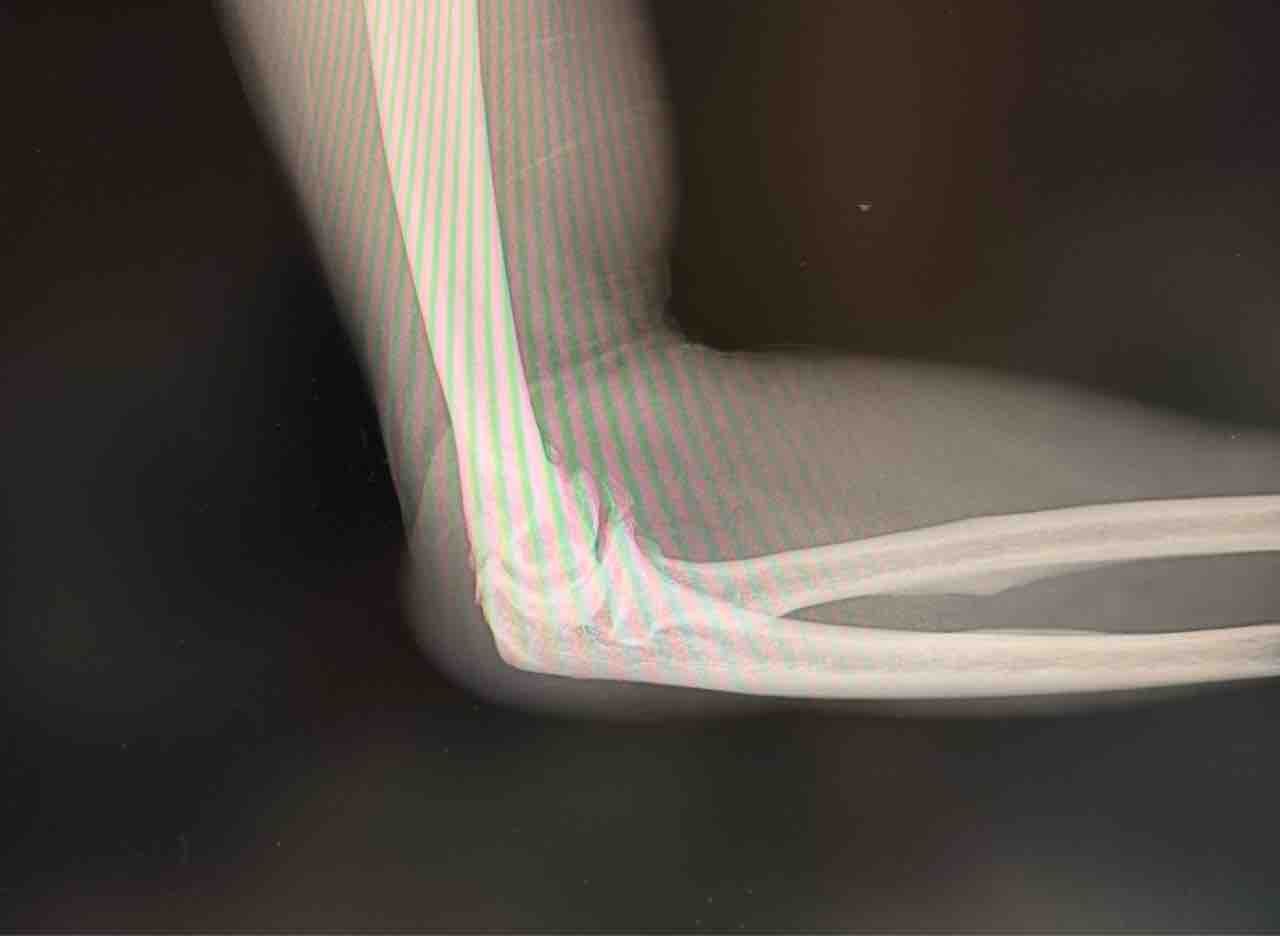

20261月29 修行のじかん(笑) 修行のじかん(笑)▼22:10追記飲み始めてすでに二時間。まだ1.5ℓ弱。ビールだったら2ℓに一時間もかからんのに(笑)。▼23:40追記これまでよりなんか飲みやすいと思ったら、よく混ざってなかった(笑)。残りは濃すぎて、さらに水で薄めて増量。まだ500cc弱残ってる(ノ_<)▼25:47追記終了▼修行のとき、終了(笑)▼その後、馴染みの外科で久しぶりに肘の水抜き(笑)骨が変形し、ないところに骨ができてるらしい^ ^;今回はヒールフックでポストした時に痛めたやつ。身体の耐久力は加令と共に確実に落ちてるから、やり方を工夫しないとね^ ^ 「日記」カテゴリの最新記事 コメント コメントフォーム 名前 コメント 評価する リセット リセット 顔 星 投稿する 情報を記憶